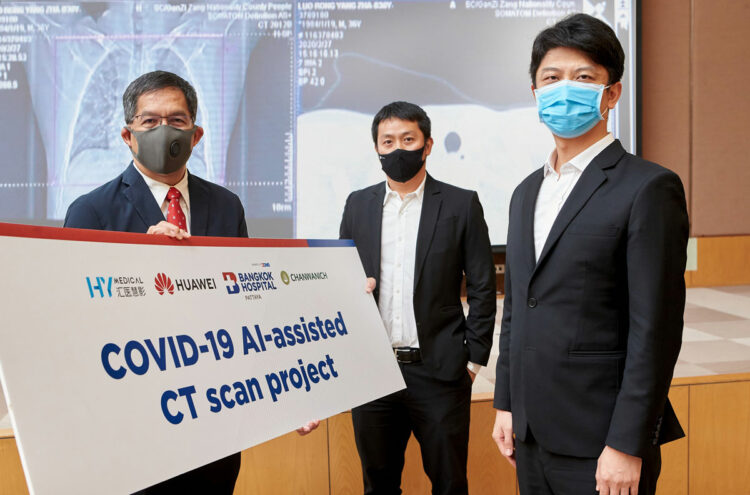

โรงพยาบาลกรุงเทพพัทยา ร่วมกับหัวเว่ย และจันวาณิชย์ นำโซลูชัน AI เสริมการรักษาโควิด-19 เป็นโรงพยาบาลเอกชนแห่งแรกในอาเซียนเพื่อช่วยสนับสนุนบุคลากรทางการแพทย์

โรงพยาบาลกรุงเทพพัทยา ในเครือ BDMS ร่วมกับ บริษัท หัวเว่ย เทคโนโลยี่ ประเทศไทย (จำกัด) บริษัท HY Medical จากประเทศจีน และ บริษัท จันวาณิชย์ จำกัด (Chanwanich) ร่วมกันพัฒนาเทคโนโลยีปัญญาประดิษฐ์ หรือ Artificial Intelligent (AI) มาช่วยในการคัดกรองและวินิจฉัยตรวจรอยโรคสำหรับผู้ป่วยที่เข้ารับการรักษา COVID-19 ซึ่งเป็นเทคโนโลยีที่ประสบความสำเร็จในการฝ่าวิกฤต โควิด-19 ของประเทศจีน และถือได้ว่า โรงพยาบาลกรุงเทพพัทยา ในเครือ BDMS เป็นโรงพยาบาลเอกชนแห่งแรกในภูมิภาคอาเซียนที่ได้นำเทคโนโลยีดังกล่าวมาใช้ เพื่อช่วยสนับสนุนบุคลากรทางการแพทย์ให้ได้มีความพร้อมในการคัดกรองและวินิจฉัยได้ถูกต้องและแม่นยำมากขึ้น

โรงพยาบาลกรุงเทพพัทยา ในเครือ BDMS ทำหน้าที่สนับสนุนบุคลากรทางการแพทย์ พร้อมทั้งทดสอบการใช้งานและรับการถ่ายทอดเทคนิค วิเคราะห์ร่วมกับผู้เชี่ยวชาญจากประเทศจีน โดยได้รับการสนับสนุนเทคโนโลยีจากหัวเว่ย และ HY Medical เป็นผู้ถ่ายทอดแนวคิดและบทเรียนสำหรับแนวทางการติดตั้งระบบ ผ่านระบบการสื่อสารทางไกลจากประเทศจีน โดยมีบริษัท Chanwanich เป็นผู้นำมาประยุกต์ใช้กับการทำงานให้เหมาะสมกับประเทศไทย ในโครงการฯ ได้มีการระดมความคิดเห็นร่วมกันทั้งจากแพทย์ผู้เชี่ยวชาญด้านรังสีวิทยา และการวิเคราะห์ภาพถ่าย X-Ray และ CT-Scan พร้อมทั้งฝ่ายสนับสนุนสารสนเทศของทางโรงพยาบาล และระบบสนับสนุนทางเทคนิคของทีมงานทั้ง 4 ฝ่าย ที่ปรึกษาและผู้เชี่ยวชาญจากประเทศจีน เพื่อทำให้ระบบสามารถใช้งานได้อย่างดี

โซลูชัน AI บน HUAWEI CLOUD จากหัวเว่ยทำหน้าที่พิจารณาภาพ CT Scan เพื่อวิเคราะห์ว่าปอดนั้นได้รับเชื้อไวรัสโควิด-19 หรือยัง โดยยังสามารถบอกถึงระยะของการติดเชื้อว่าอยู่ในระยะเริ่มต้น ระยะลุกลาม หรือระยะรุนแรง ด้วยอัตราความแม่นยำของการวินิจฉัยภาพสูงถึง 96% และใช้เวลาในการอ่านเพียงไม่กี่วินาที จึงมีประสิทธิภาพอย่างยิ่ง ปัจจุบัน มีโรงพยาบาลในประเทศจีนกว่า 20 แห่ง นำโซลูชั่นนี้ไปปรับใช้เพื่อรับมือกับสถานการณ์โควิด-19 สำหรับในประเทศไทย ทางหัวเว่ยได้มอบโซลูชันดังกล่าวให้แก่โรงพยาบาลรามาธิบดีและโรงพยาบาลศิริราช เมื่อเร็วๆ นี้

บริษัท จันวาณิชย์ จำกัด (Chanwanich) ได้ส่งทีมพัฒนาและสนับสนุนเพื่อทำภารกิจ การถ่ายทอดองค์ความรู้และเทคโนโลยีมาสู่ประเทศไทยได้สำเร็จ พร้อมทั้งยังทำหน้าที่ขับเคลื่อนเชื่อมโยงการดำเนินงานทั้งหมด เพื่อทำให้เกิดการใช้งานได้อย่างรวดเร็ว โดยใช้เวลาเพียง 2 สัปดาห์ในการหารือ ติดตั้งระบบและเริ่มใช้งานจริง Chanwanich มุ่งมั่นที่จะพัฒนาระบบสุขภาพและสาธารณสุข เพื่อยกระดับความสามารถทางการแพทย์ให้กับคนไทย เพื่อเข้าสู่การเป็น “Integrated Health Solutions”